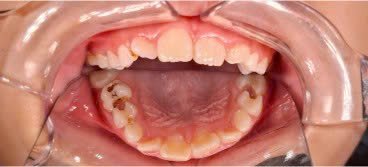

Nếu mất răng sữa sớm, các răng xung quanh di chuyển vào khoảng trống mất răng, dẫn đến thiếu khoảng mọc cho răng vĩnh viễn sau này, gây tình trạng răng vĩnh viễn mọc chen chúc, lệch lạc hoặc mọc ngầm.

Răng sữa giúp răng vĩnh viễn mọc đúng vị trí. Nếu răng sữa bị sâu, viêm nhiễm không được điều trị, nhiễm trùng có thể ảnh hưởng mầm răng vĩnh viễn bên dưới về hình dạng và màu sắc và chất lượng mô răng.